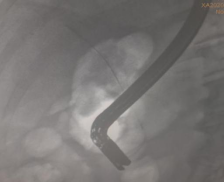

胆管插管成功,导丝进入胆管内……

(胆管插管成功,导丝进入胆管内) (胆管支架植入,解除胆道梗阻和胆道高压)

凭借扎实的ERCP专业功底和内镜操作技能,ERCP团队在短短20分钟就顺利完成了ERCP+EST+取石+ERBD+ENBD术,即胆总管造影、十二指肠乳头切开、胆总管末段嵌顿结石取出、胆总管支架植及鼻胆管引流术系列手术操作。

(ERCP术后胆管支架、鼻胆管X光线图片)